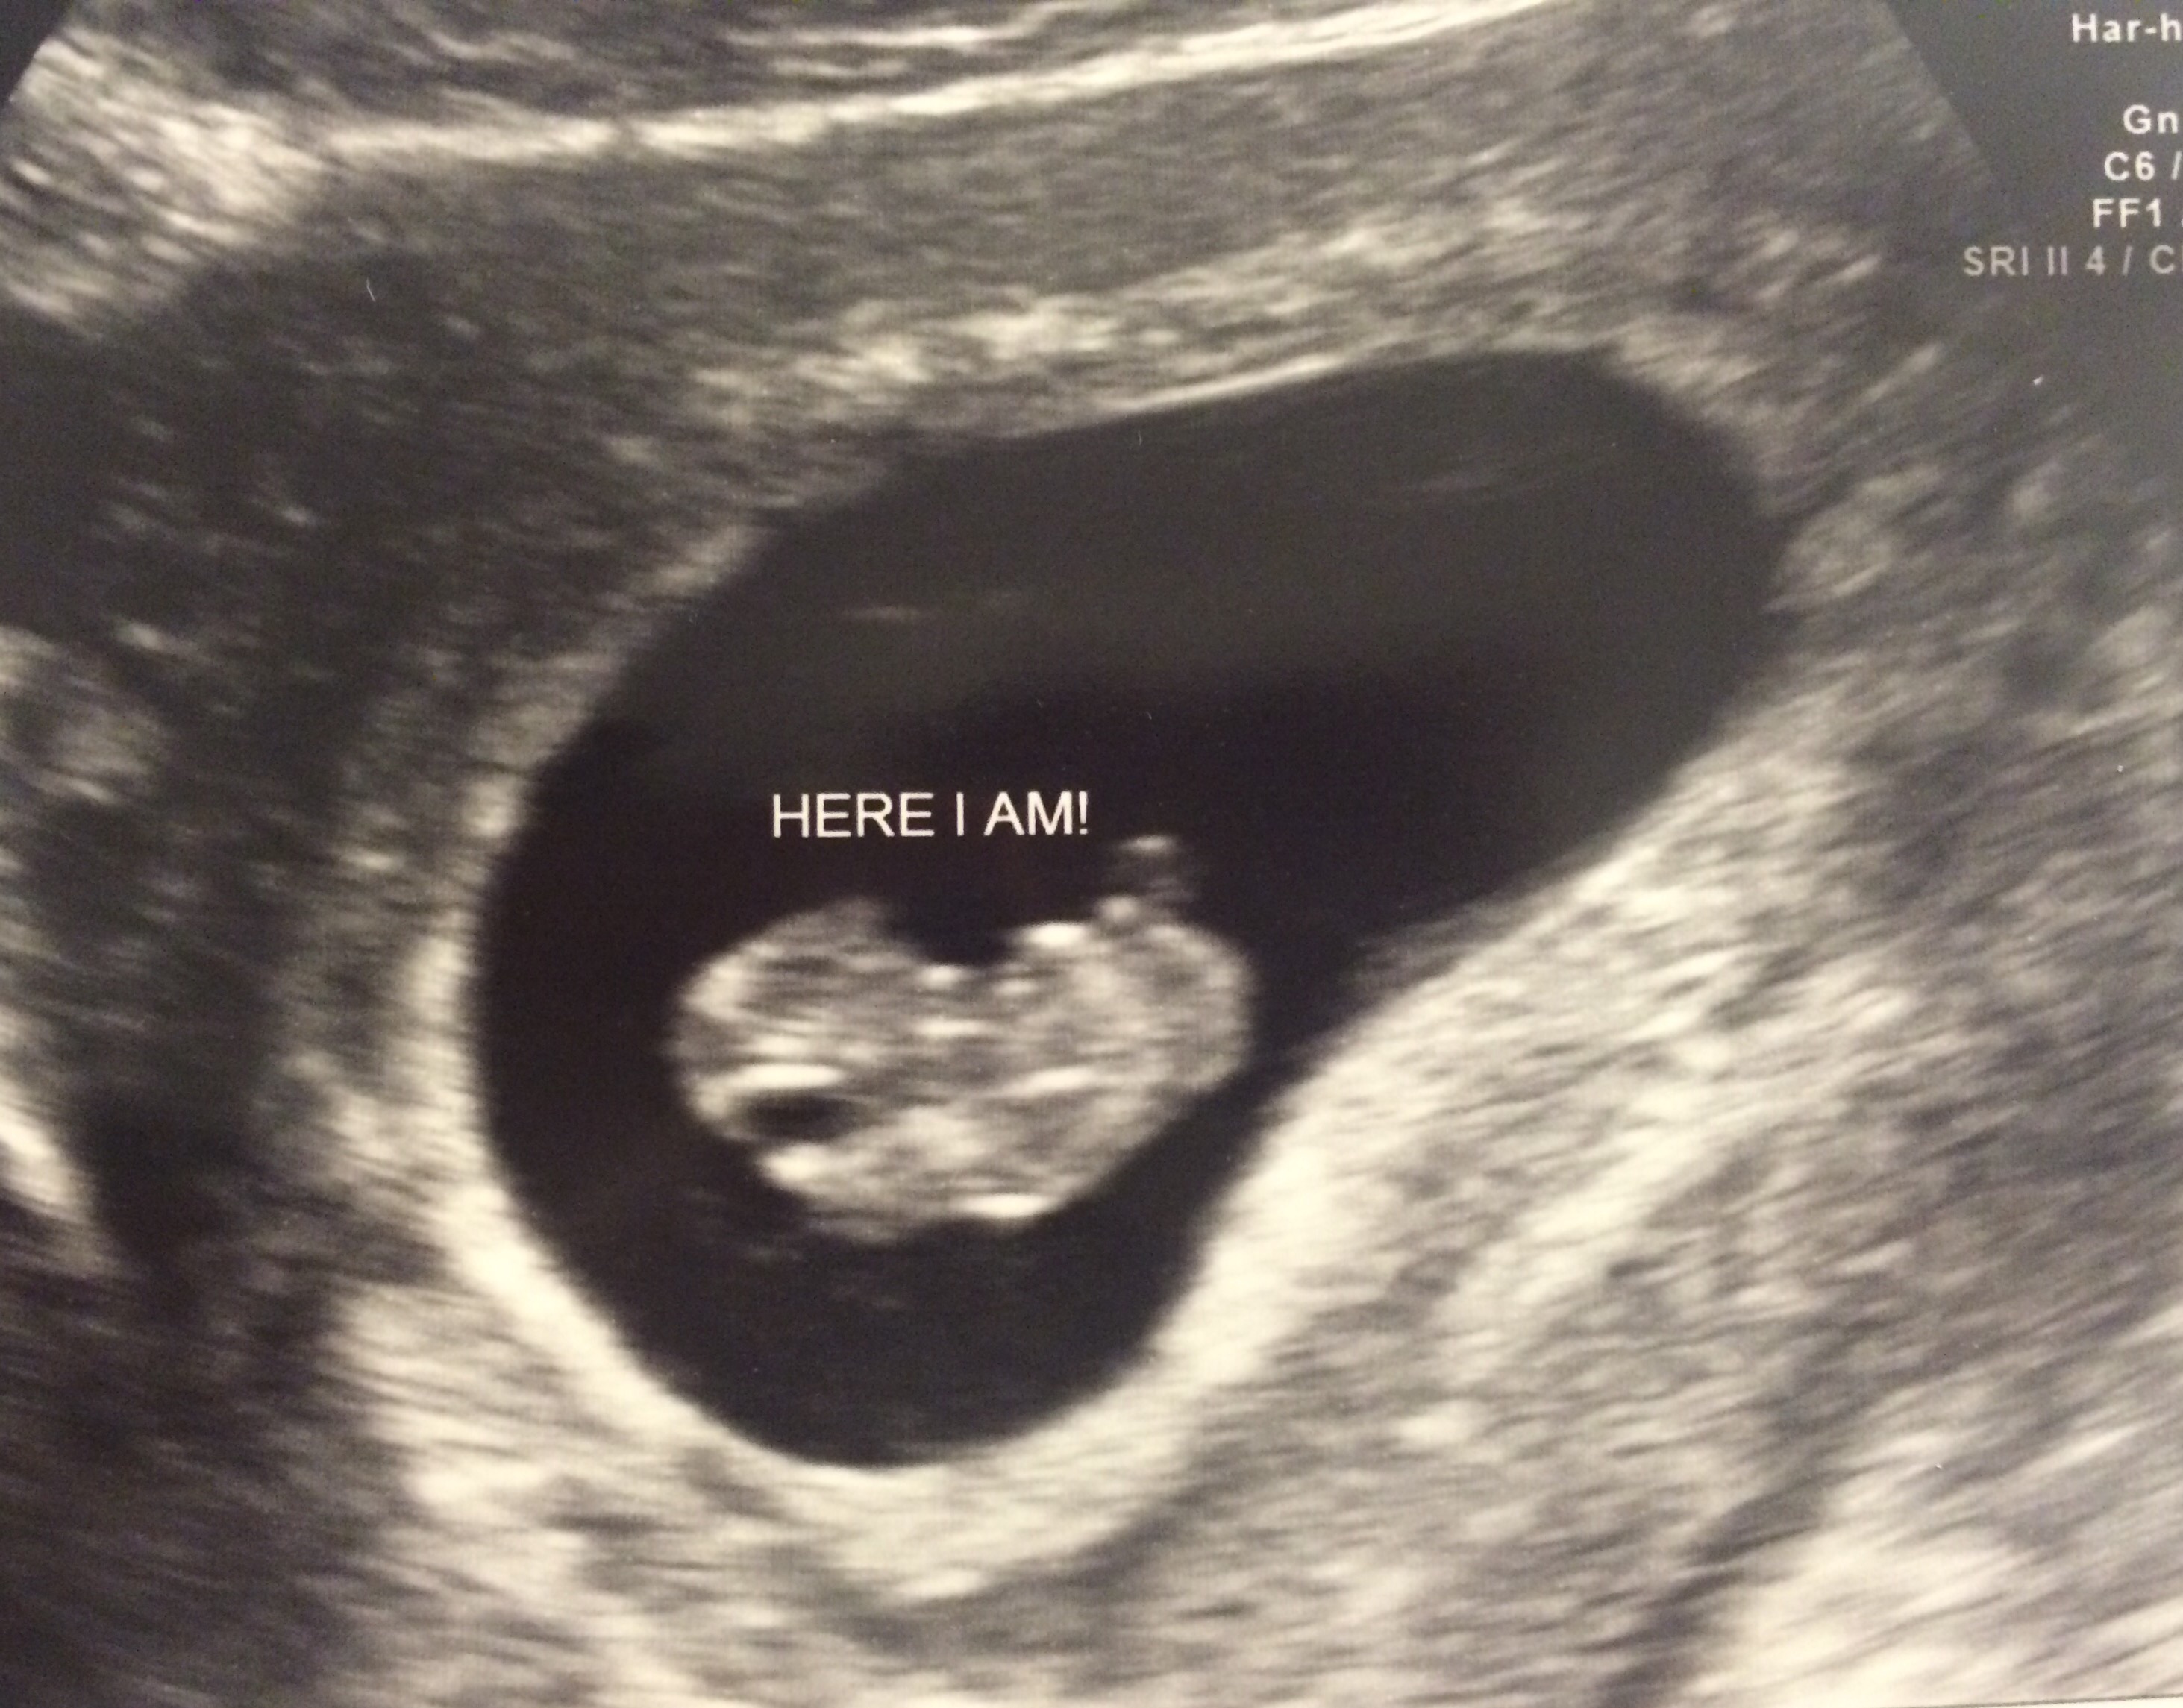

Finally got to see our peanut.

image